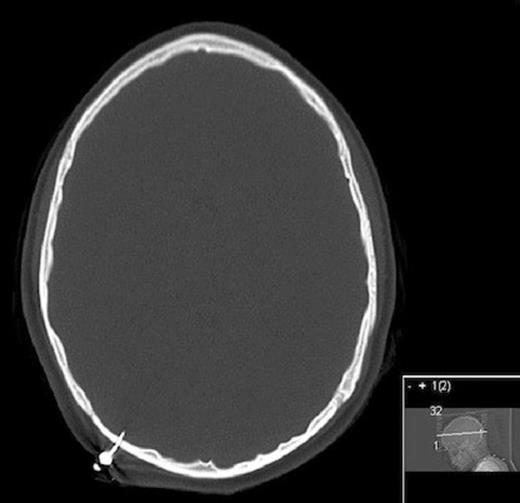

Patient was taken to the operating room and a craniectomy was performed for removal of the dart. It was noted that the dart traversed the entire skull leaving a small hole and was tightly adherent to the skull (figure 4). The outer layer of dura was penetrated and had a blue discoloration likely from heating, however no csf leak was noted. An appropriate sized burr hole cover was placed over the craniectomy site. The wound was washed out and the incision closed with vertical mattress sutures. The patient did well postoperatively and was discharged within two post-operative days.

Intraoperative picture showing entry site after extracranial portion broke off